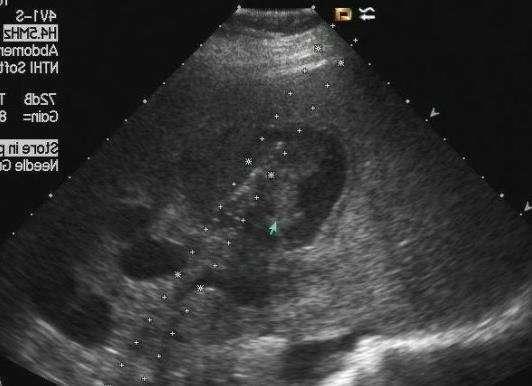

案例图:乙肝病史十年 超声显示肝实质回声增粗,增强

所以,根据这位读者是一位乙肝患者,近期又有脸黄症状,可优先排查肝功能、肝脏B超、病毒载量等指标。针对健康人出现脸黄,比如读者的家人是没有感染乙肝的情况,要优先排查以上非疾病原因,然后才是疾病原因引起。